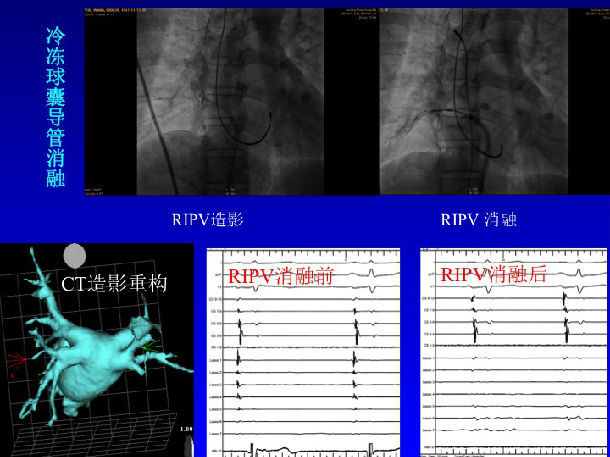

冷冻球囊导管消融举例: